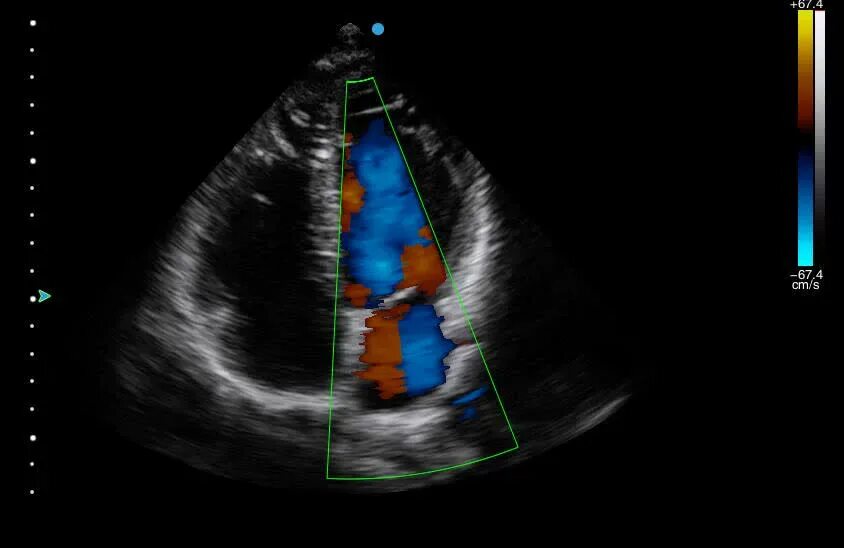

Допплер эхокардиография. эхо кг допплер. допплер узи сердца.

Допплер эхокг сердца. апикальная позиция эхокг. методика проведения эхокардиографии. эхокардиография (узи сердца эхо кг).

Аортальный стеноз допплер эхокг. допплерография при митральной недостаточности. допплер узи сердца. аортальная регургитация на эхокг.